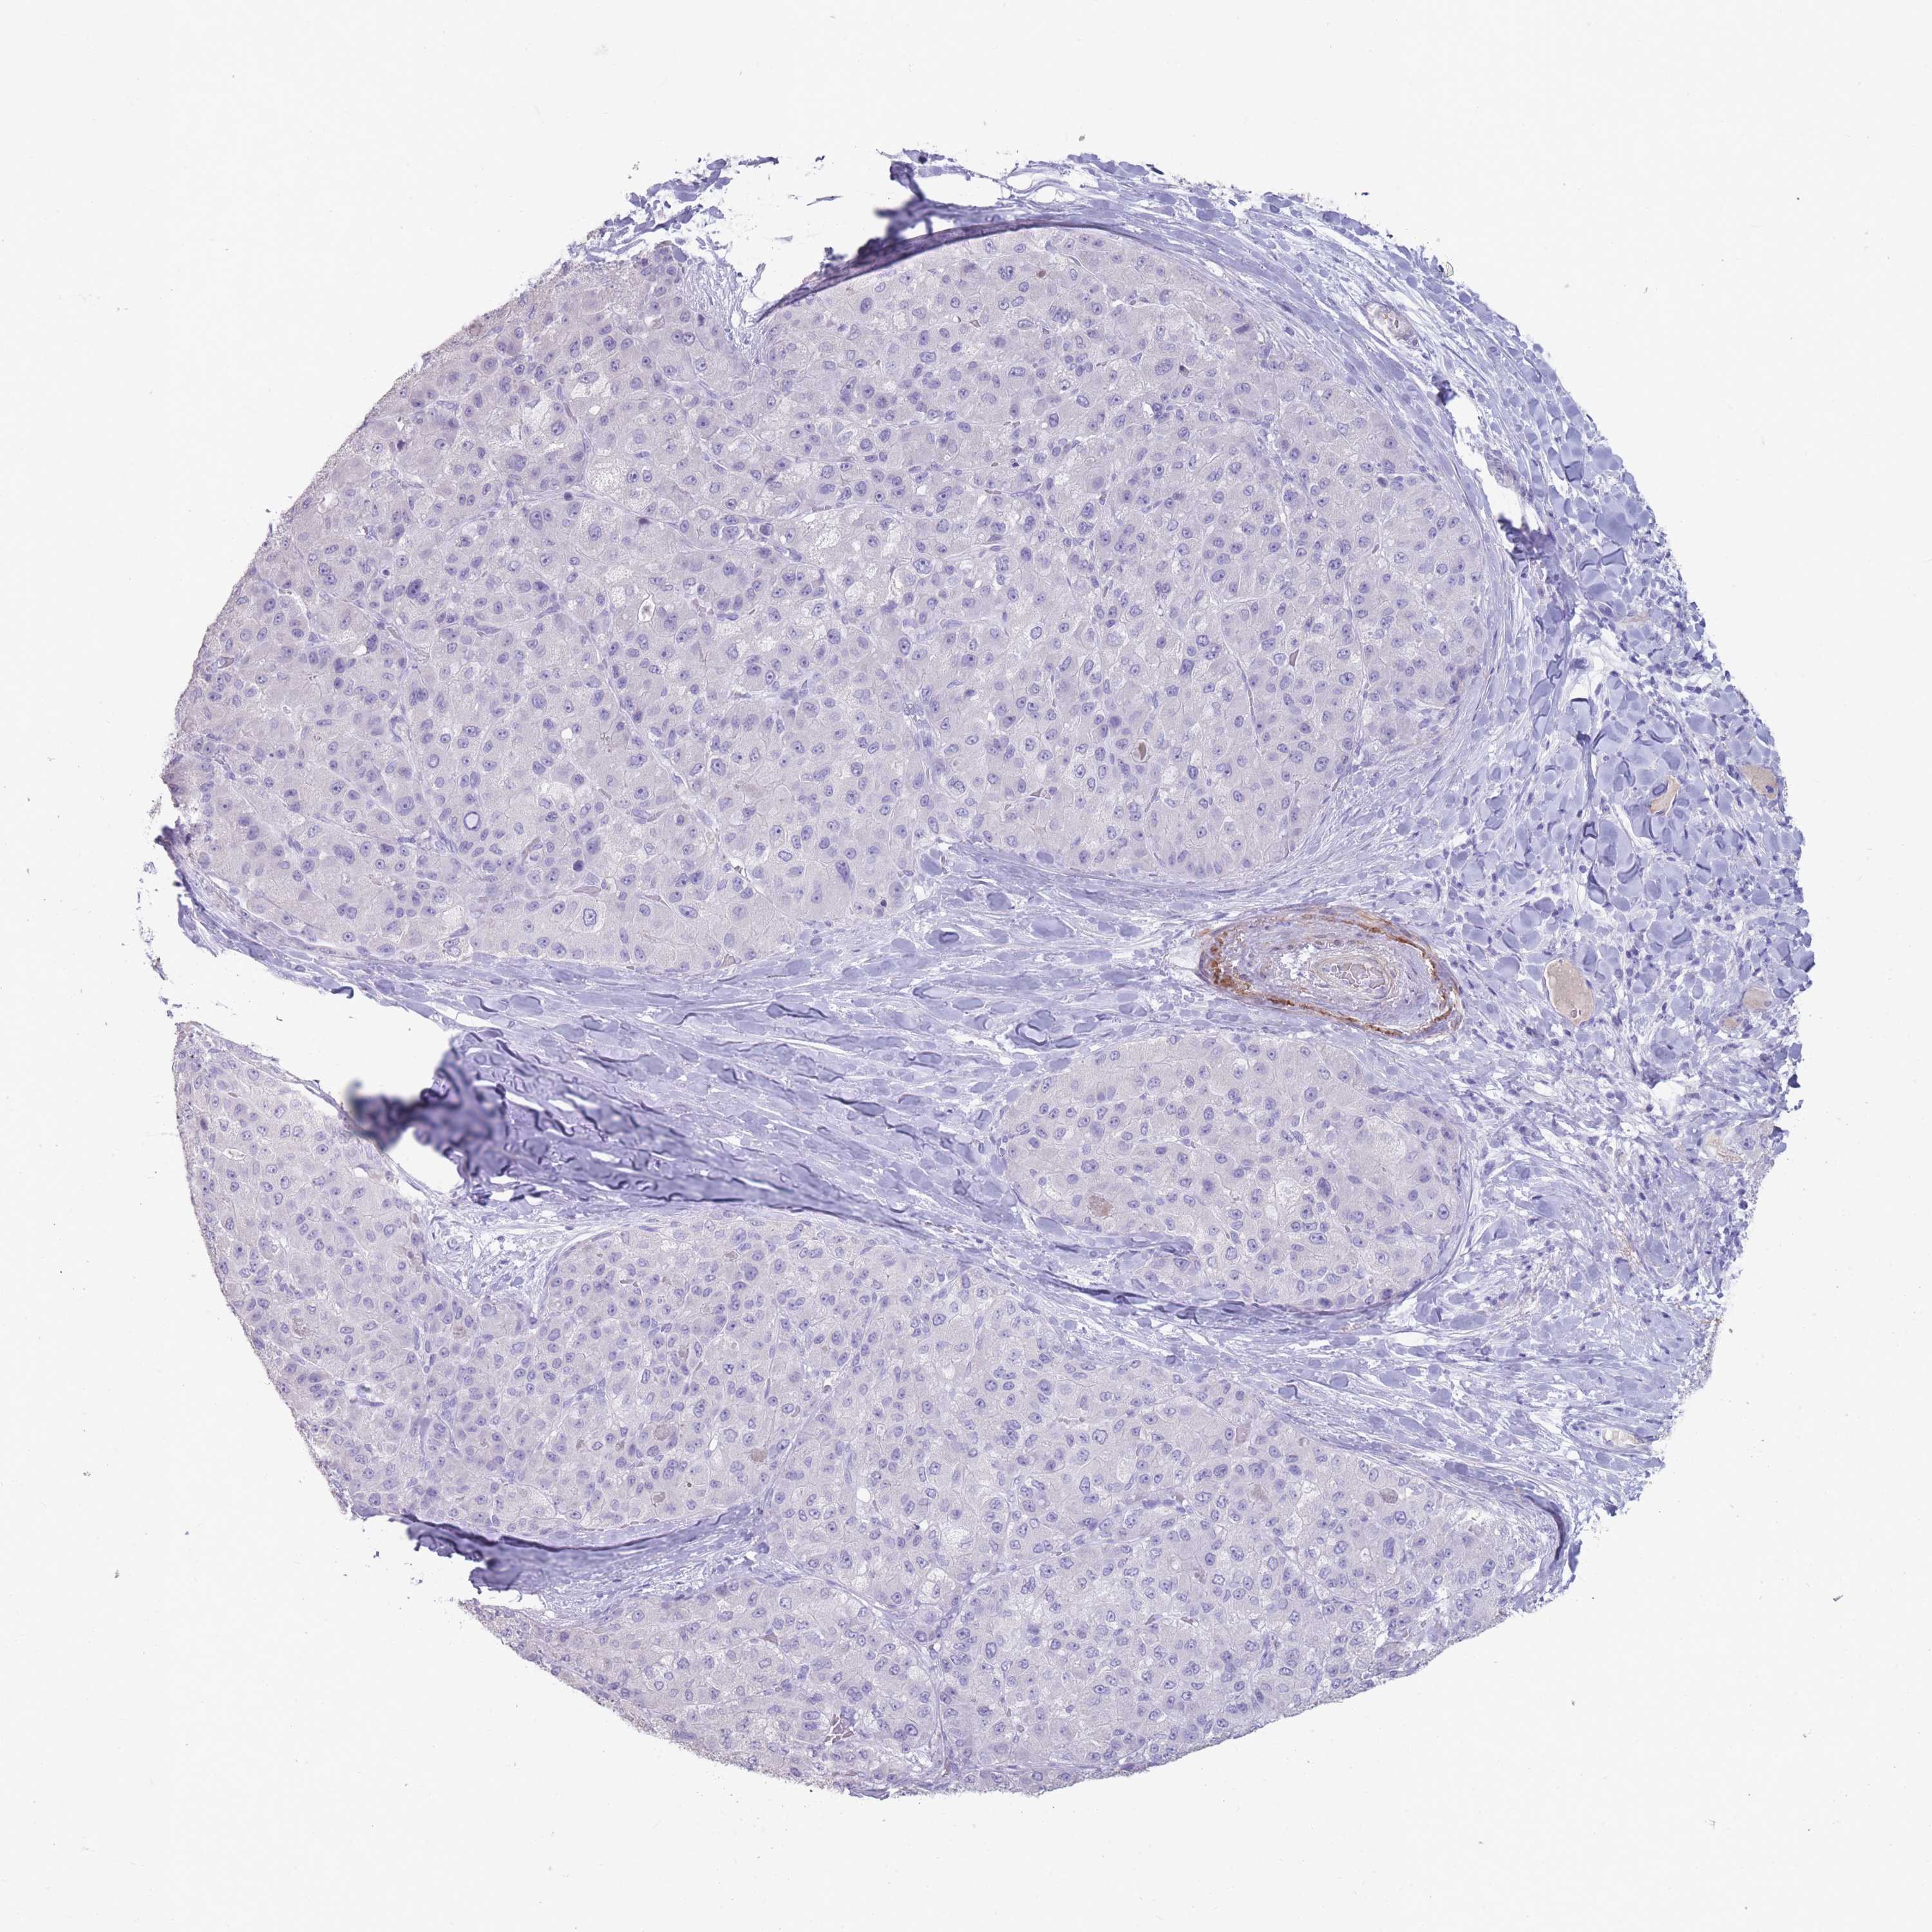

LIVER CANCER - Protein expressioni

A mouse-over function shows sample information and annotation data. Click on an image to view it in a full screen mode. Samples can be filtered based on level of antibody staining by selecting one or several of the following categories: high, medium, low and not detected. The assay and annotation is described here.

Note that samples used for immunohistochemistry by the Human Protein Atlas do not correspond to samples in the TCGA dataset.

Antibody stainingi

Antibody staining in the annotated cell types in the current human tissue is reported as not detected, low, medium, or high, based on conventional immunohistochemistry profiling in selected tissues. This score is based on the combination of the staining intensity and fraction of stained cells.

Each image is clickable and will lead to virtual microscopy that enables deeper exploration of all samples and also displays staining intensity scores, fraction scores and subcellular localization as well as patient and tissue information for each sample.

Antibody HPA048489

Staining

High

Medium

Low

Not detected

Intensity

Strong

Moderate

Weak

Negative

Quantity

>75%

75%-25%

<25%

None

Location

Nuclear

Cytoplasmic/membranous

Cytoplasmic/membranous,nuclear

Cholangiocarcinoma

Carcinoma, Hepatocellular, NOS